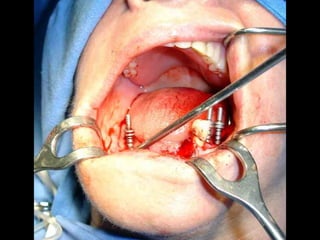

Primer tiempo quirúrgico; Exposición del maxilar para tomar una impresión del

hueso y poder elaborar la estructura implantaria.

Segundo tiempo quirúrgico para aplicar la estructura.

Segundo tiempo quirúrgico: